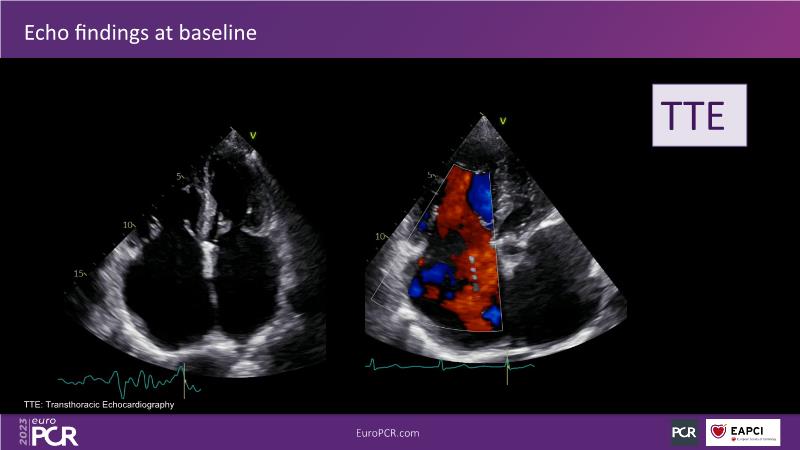

Tailoring tricuspid regurgitation patient treatment with the PASCAL Precision system

Watch this session to discuss exciting cases of tricuspid regurgitation, learn about the proposed new integrated classification for tricuspid regurgitation and enjoy a live presentation of the PASCAL Precision Repair System using a beating heart simulator, among others!

- To discuss the different tricuspid regurgitation phenotypes that can be treated with the PASCAL Precision repair system

- To participate in a case-based discussion using the PASCAL Precision repair system for the treatment of tricuspid regurgitation